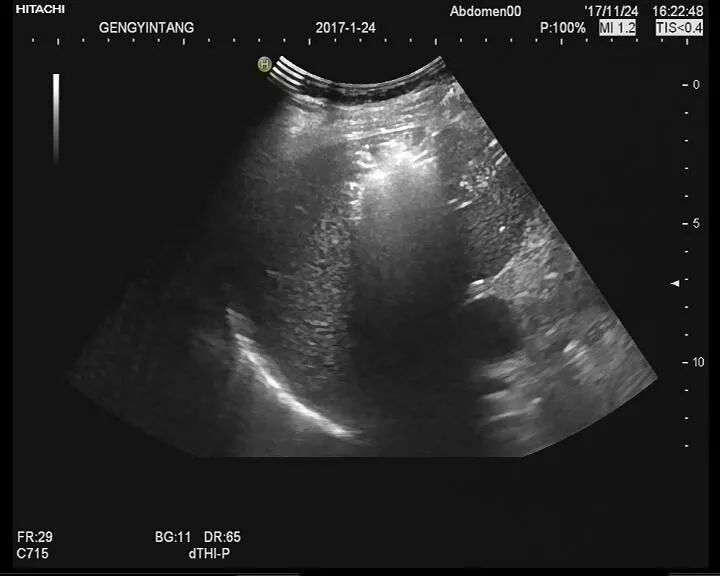

如果血清β-hCG定量<5mIU/mL,可排除异位妊娠。如果超声发现宫内妊娠囊,异位妊娠的可能性极小,除非是采用辅助生殖技术的妇女(辅助生殖技术增加了宫内宫外同时妊娠的风险);然而宫角妊娠和腹腔内妊娠可能有类似于宫内妊娠的超声表现。提示异位妊娠的超声检查表现(检出率16%~32%)包括混合性包块(囊实混合性),尤其是附件区包块以及子宫直肠陷凹游离液体。

3、超声

如果血清β-hCG水平高于一定水平(称为分界区),宫内妊娠孕妇在超声检查时可发现孕囊。该水平通常是约2000mIU/mL。如果β-hCG高于分界区但没有发现宫内妊娠囊,提示可能为异位妊娠。应用经阴道超声和彩色多普勒超声可提高检出率。